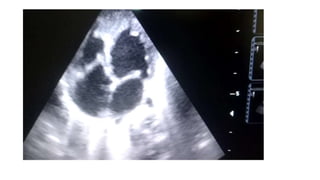

ECHOCARDIOGRAPHY

• “Displacement Index” is measured in systole or diastole from the

insertion point of the anterior mitral leaflet to the hinge point of

the tricuspid septal leaflet

• displacement index >8 mm/m2 -diagnosis of Ebstein anomaly

• determination of forward flow through RVOT and across the

pulmonary valve

• difficult in the neonatal setting with elevated pulmonary vascular

resistance

• pulmonary regurgitation -differentiate anatomic atresia from the

more common “functional” atresia of the pulmonary valve